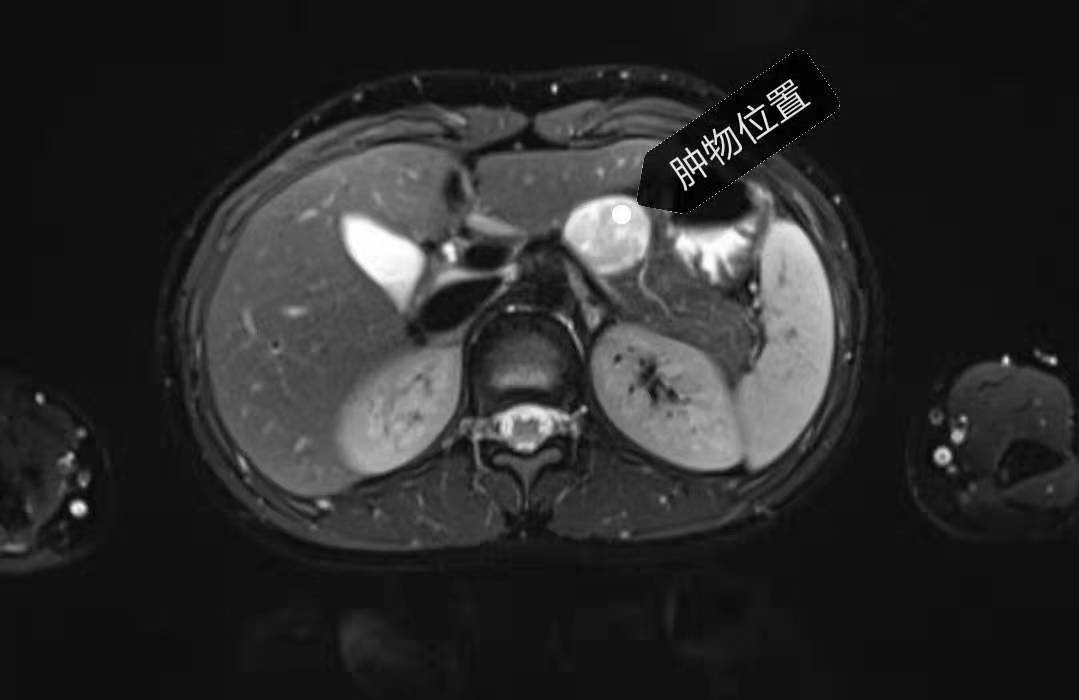

13岁女孩小叶(化名),由于上腹部胀痛难忍长达3个月,来医院检查后发现体内竟藏着一个3—4厘米大的胰体肿瘤,考虑“实性假乳头状瘤”可能,建议手术切除。常规的手术计划是连同胰尾和脾脏一并切除以降低难度,但创口面至少20公分以上。胰尾又含有大量的胰岛,切除后有患糖尿病风险。脾脏是人体的重要免疫器官,对维持人体正常血细胞水平、免疫功能等有重要作用。无论是从美观还是身体机能需要的角度,常规手术都不适合她。